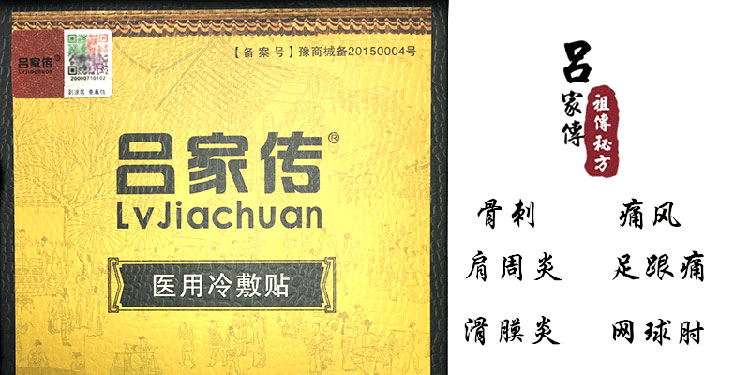

【产品名称】:吕家传冷敷贴